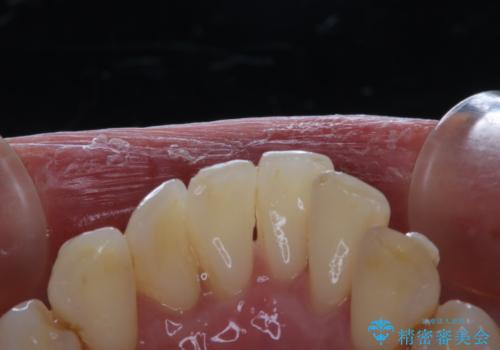

マウスピース矯正インビザライン治療では、歯の表面にアタッチメントという突起を設定します。(アタッチメントは歯の動きを効率的に移動するためのものです)

アタッチメントが歯に付くと、表面が凸凹し磨き残しが多くなったりと、プラークや歯石・着色がつきやすくなることがあります。

矯正治療中もPMTCを定期的に行い、専門的な機械でしっかりと汚れを除去することがおススメです。